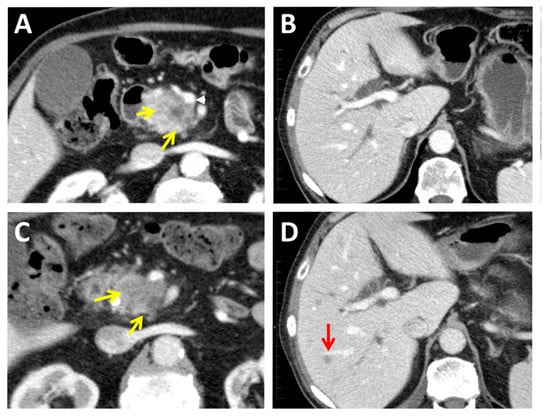

2.1. Computed Tomography

2.3. Magnetic Resonance Imaging